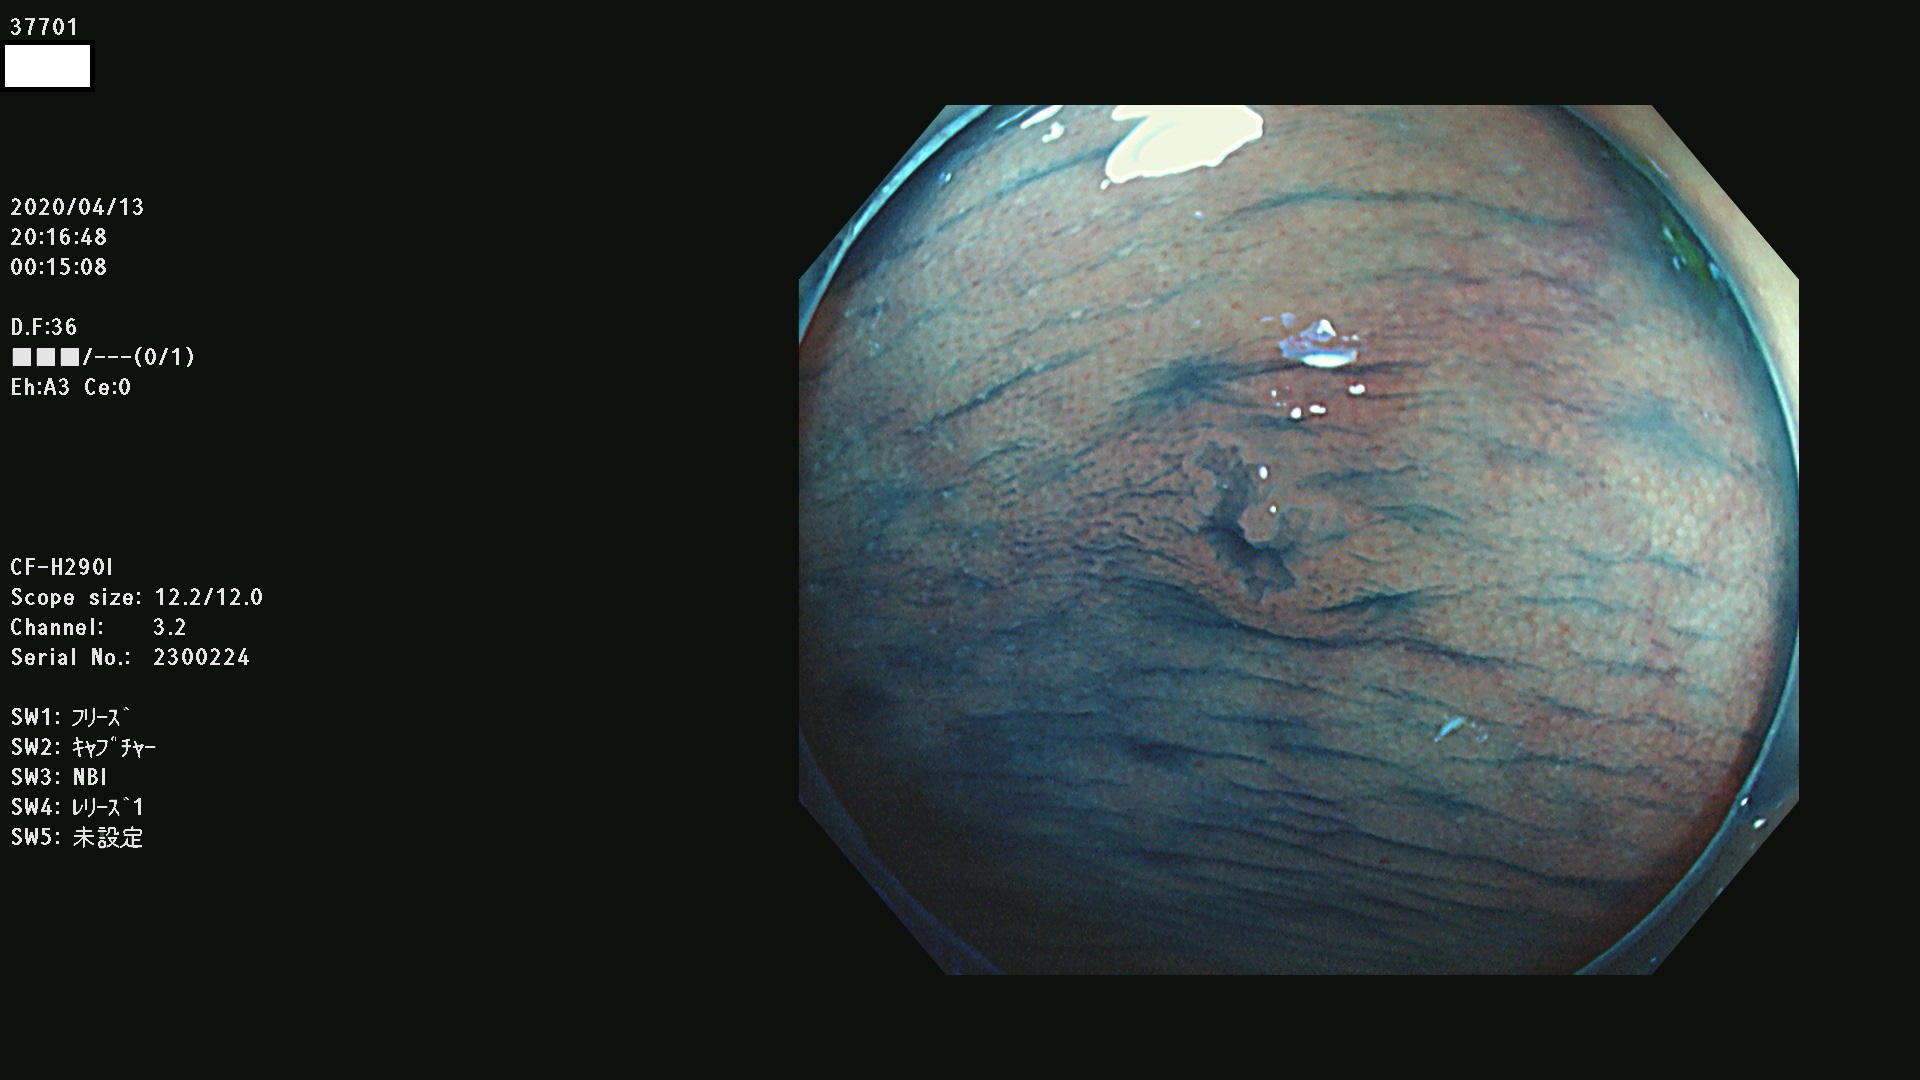

37700 37701 37702 37703 37704 37705 37706 37707(SSAPのみ) 37709 37711 37712 37715 37716 37717 37720 37722(SSAPのみ) 37724 37725 37726 37727 37728 37729 37731 37732 37733 37736(SSAPのみ) 37737 37739 37740 37741 37742 37744 37745 37748 37749 37750 37751 37752(SSAPのみ) 37753 37754 37755 37757 37758 37760 37761 37762(SSAPのみ) 37763 37764 37765 37766 37767 37768 37769 37771 37772 37774 37775 37776 37777 37780 37781 37782 37783 37784 37785 37787(SSAPのみ) 37788 37791 37792 37793 37794 37795 37799

発見困難で危険性の高い平坦型病変(上記100名より抽出)